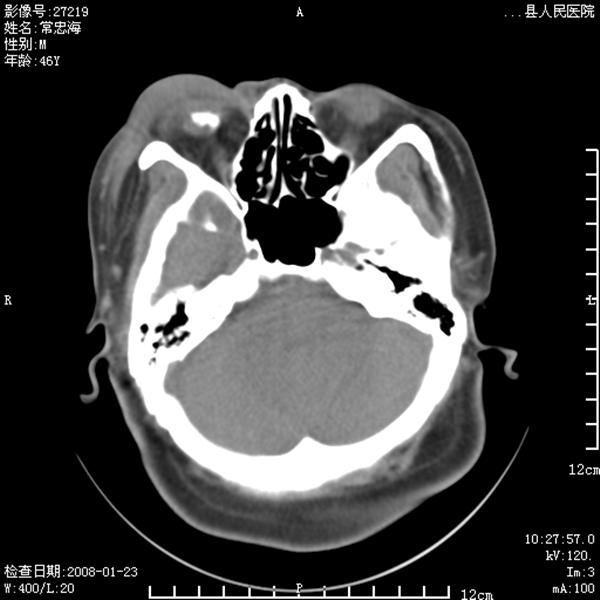

以下是引用江边学者在2008-4-19 22:26:00的发言:[br]1.胼胝体发育不良。[br]2.右侧眼球痨。[br]3.右侧颜面部软组织挫伤。